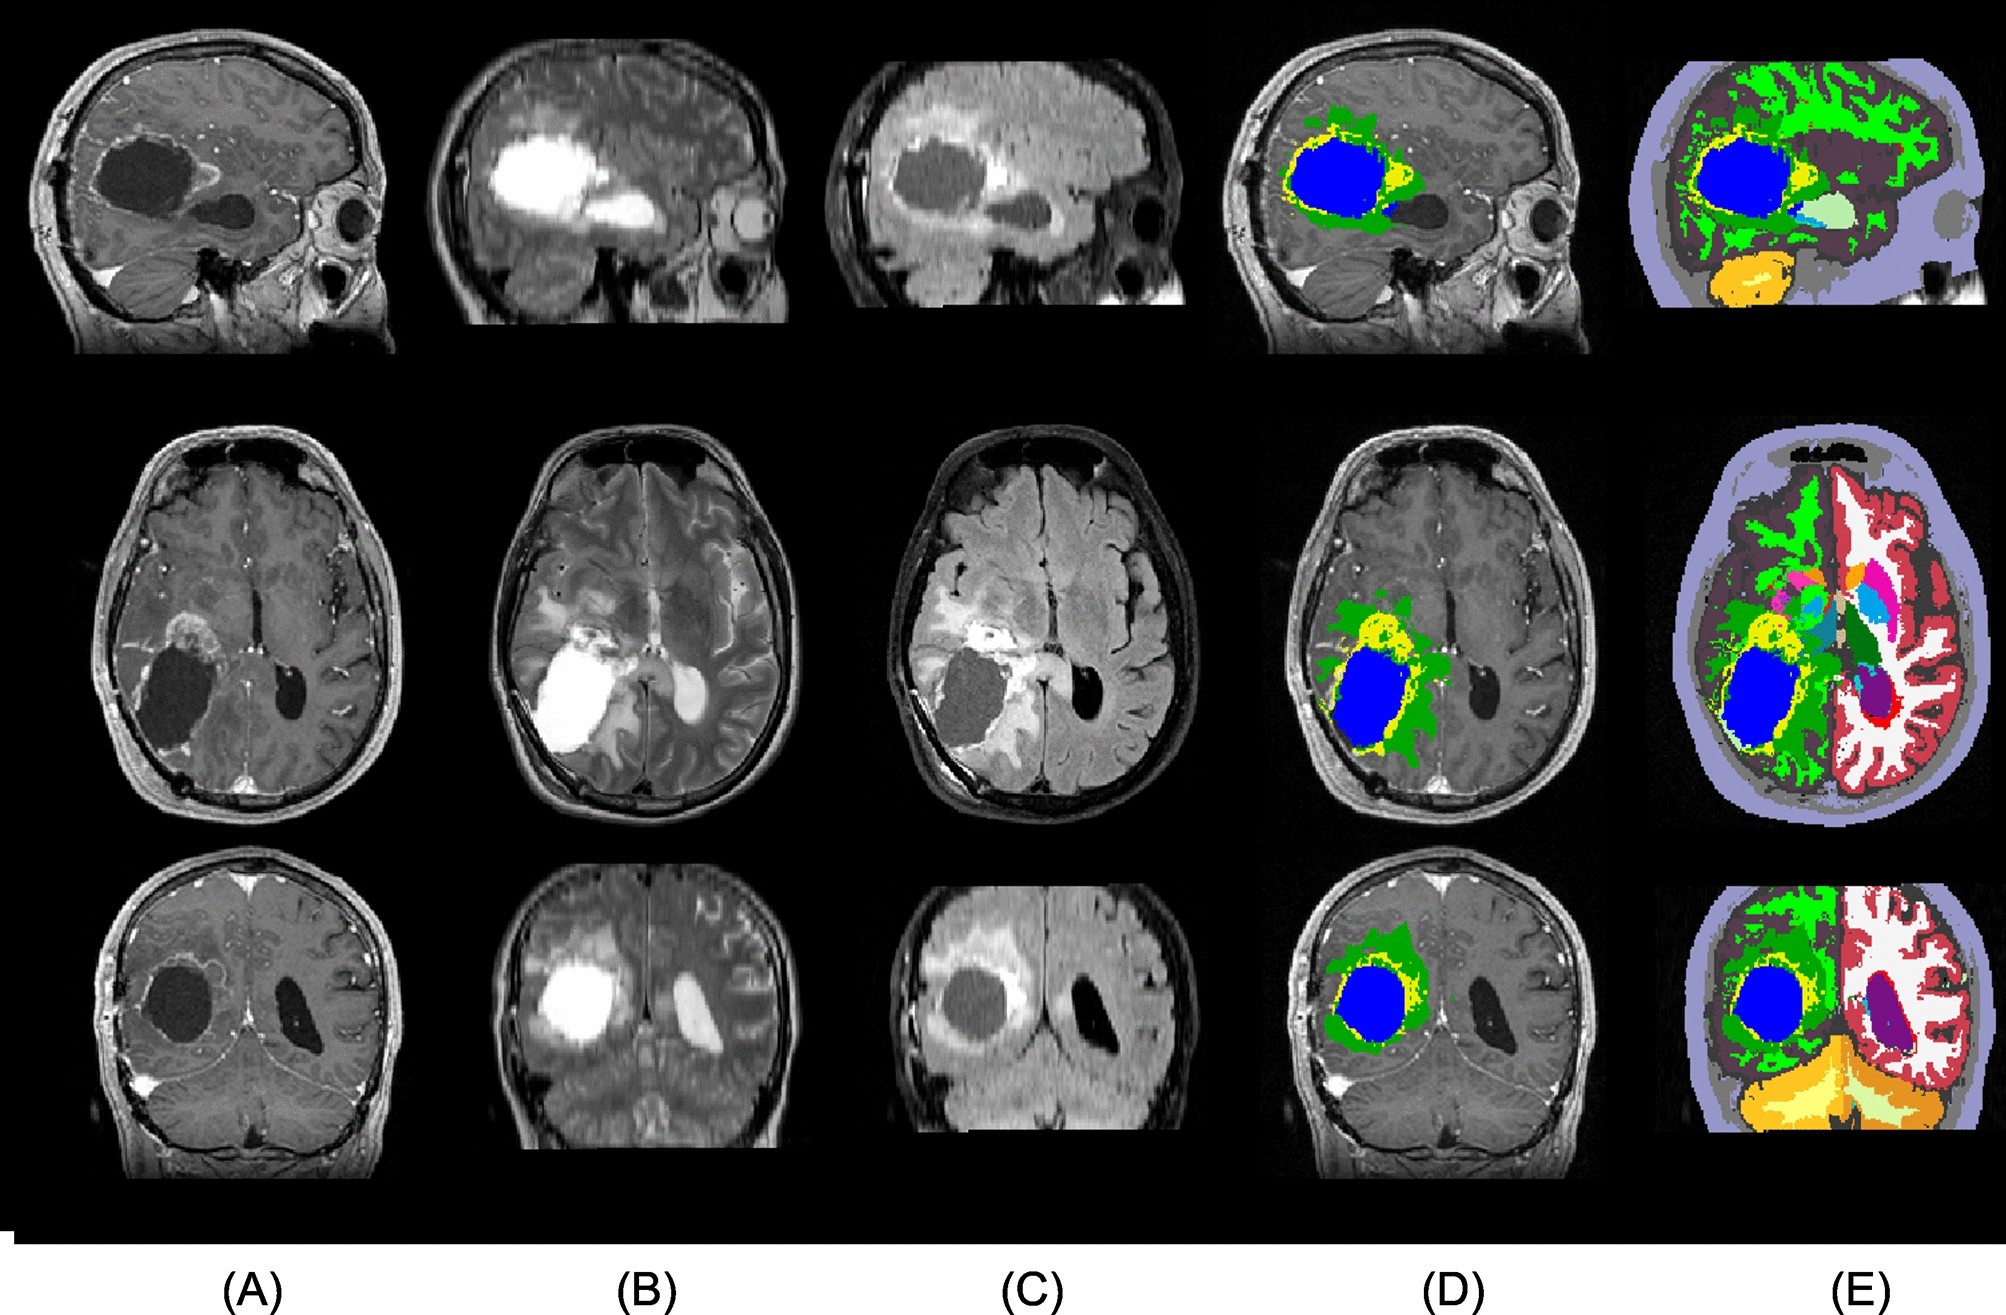

Figure 4

From: Predicting survival of glioblastoma from automatic whole-brain and tumor segmentation of MR images

A sample from the Copenhagen (post-operative) dataset. From top to bottom: sagittal, axial, and coronal view. The columns show (A) T1c, (B) T2, (C) FLAIR, and (D,E) the automatic segmentation output. (D) shows the tumor components only, while (E) shows the full segmentation output. The tumor components in (D,E) are edema (green), enhancing core (yellow), and non-enhancing core (blue). Resection cavity is shown in light-green color in the sagittal view of (E).